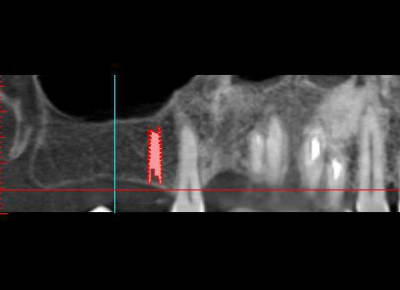

Si si! , il y a bien une image sur chacune des deux coupes.

ps: c'est vrai que après coup, on voit une densité différente sur les coupes avec une limite circulaire...

je ne l'aurai pas vu avant après en ouvrant très très grand les yeux on trouve !

sinon, j'avoue en toute honneteté n'avoir rien détecté lors de l'étude du scanner. aprés coup, c'est vrai que quand on sait ce qu'on doit chercher, on discerne...vaguement...

La radio montrait bien un volume osseux interessant mais l'image sous la corticale, très claire.

Lors de l'ostéotension, du liquide jaune lipidique a pissé de tous les trous, pas de sang. Os de type 4 inexploitable en l'état pour mettre les implants.